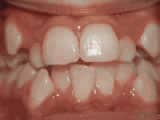

Crowding of the teeth

Before

AfterThis boy started treatment at age 11 and wore braces for 26 months. He loves his new smile.